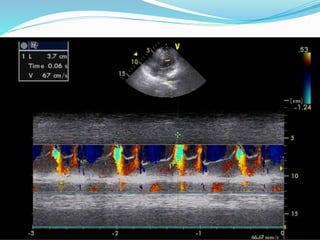

Color doppler m-mode

imaging

 Used to determine velocity of propagation (Vp) of LV

inflow.

 Determination of width of AR jet.

 Duration of MR.

Color doppler m-mode imaging Used to determine velocity of propagation (Vp) of LV inflow.  Determination of width of AR jet.  Duration of MR.